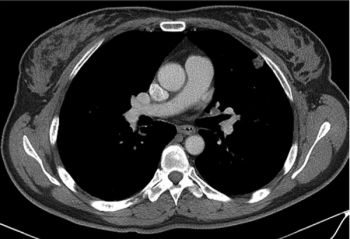

What is the diagnosis in this patient who is a 68-year-old male?